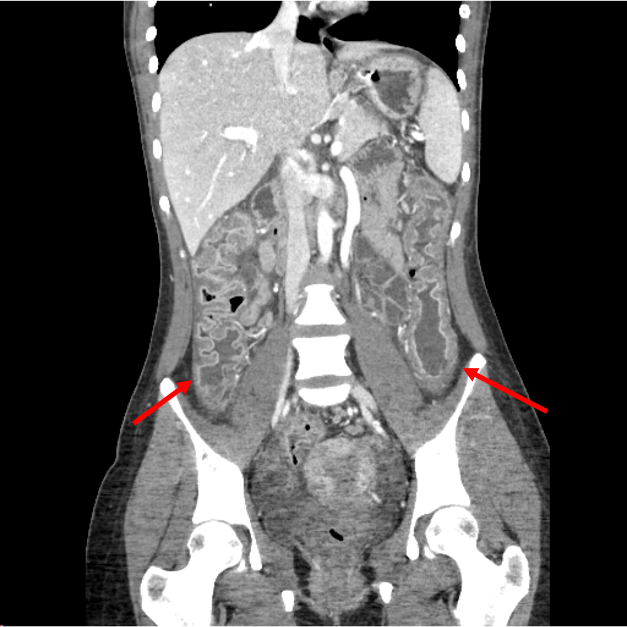

CT shows pancolitis (red arrows). There is also bilateral, symmetric sacroiliitis (blue arrows).